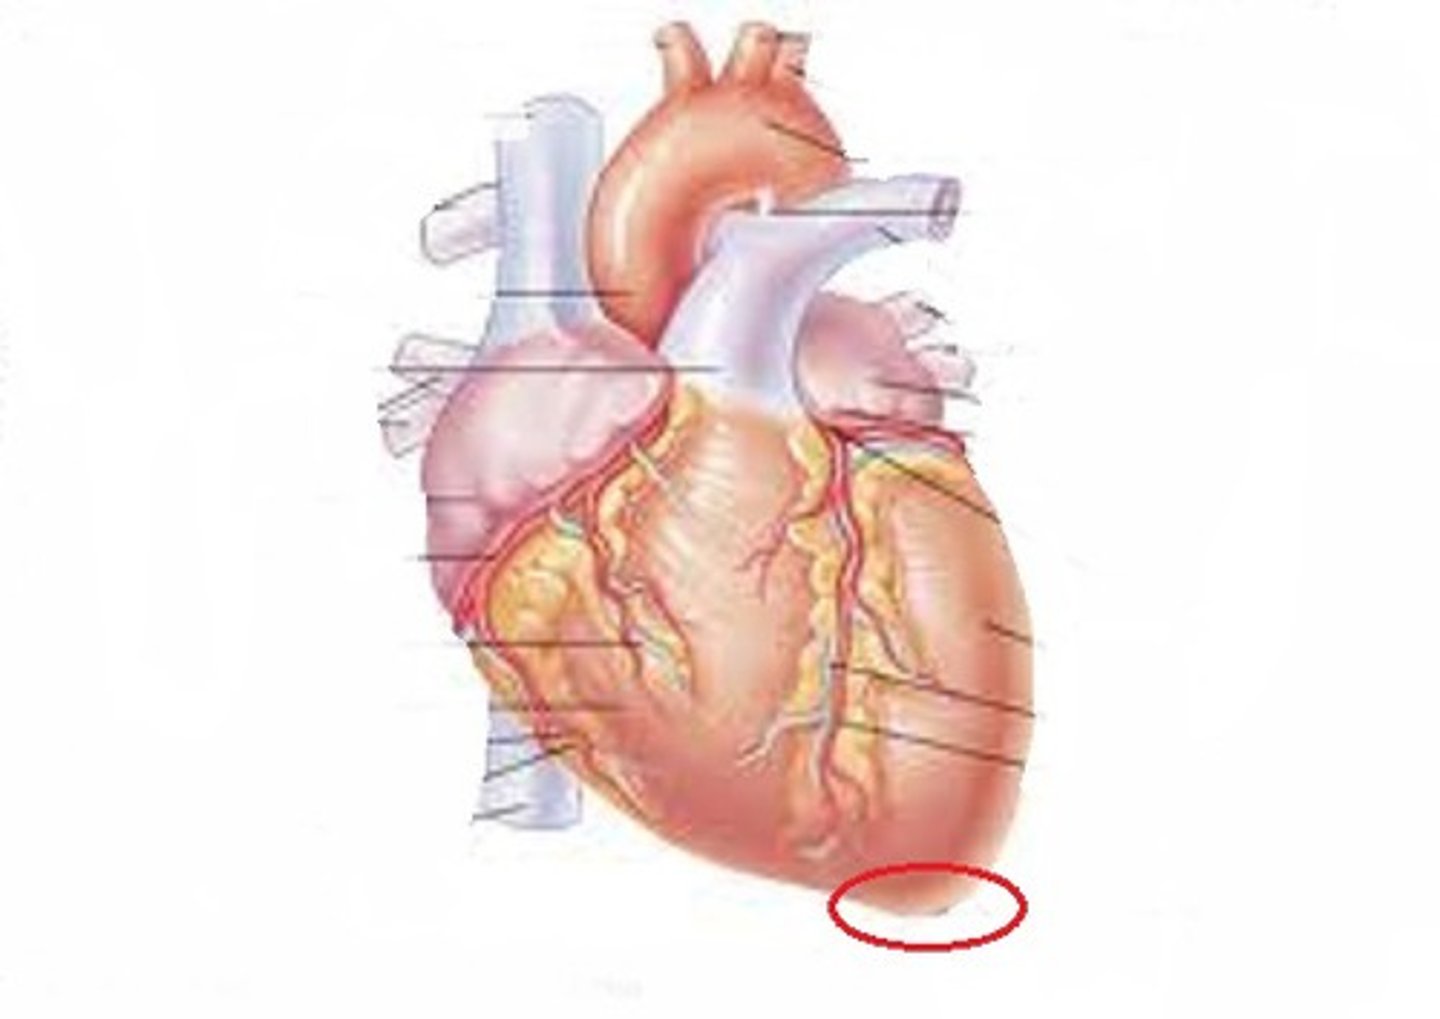

Base of the heart

Towards the right shoulder

Great vessels (pulmonary trunk and aorta) exit here

Apex of the heart

Points towards the left hip

Composed primarily of the left ventricle

Coronary arteries (right (A) and left(D))

First branch off the base of the aorta

Supplies blood to the heart muscles